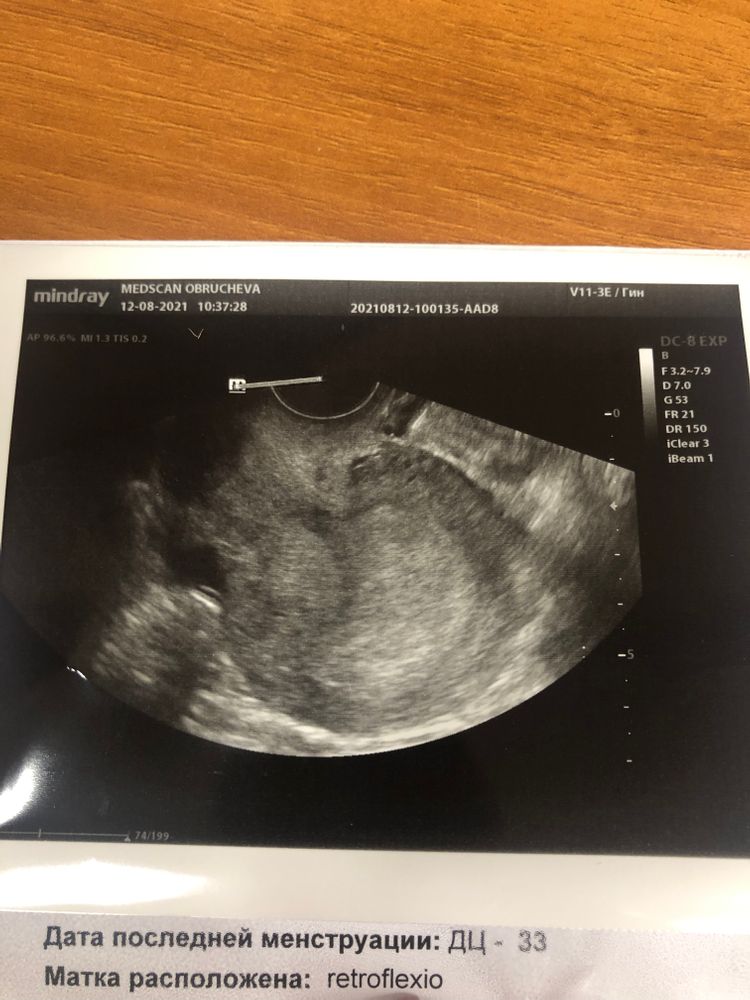

Была сегодня на узи, очень переживаю, вдруг внематочная и тд. Сдавала хгч 5 августа 34, 9 августа 261. На УЗИ: эндометрий 23 мм, жт 23 мм, плодного яйца ещё не видно. Я рано пошла?) вопрос а что это такое на фото в правом верхнем углу?

На УЗИ будет видно плодное яйцо при ХГЧ больше 1000.

Julia Tim, сейчас вроде загрузилось) я примерно посчитала у меня удвоение получается каждые 33 ч и сегодня по идее уже должно быть больше 1000 +-

Принцесса, непонятно, может быть и плодное яйцо на УЗИ, но пока очень маленькое. Ну завтра на УЗИ уже точно должно быть видно.